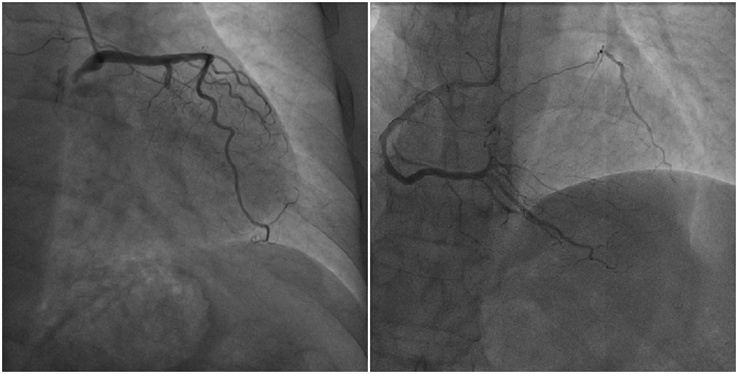

患者女性,54岁,6年前在重体力劳动时出院发作性心前区憋痛伴胸闷,伴背部发凉,自行休息10分钟左右好转,未行特殊治疗。6天前在当地医院检查时发现心电图异常,遂第二日于我院门诊完善冠脉CTA,结果示:冠状动脉呈右优势型,右冠状动脉近段及远段钙化斑块,管腔未见明显狭窄改变,左主干显影好,未见明显斑块及狭窄改变,前降支近段钙化斑块,管腔狭窄程度估测小于50%,对角支近段钙化斑块,回旋支近段混合斑块,管腔节段性闭塞改变。就诊我院行冠脉造影检查,发现回旋支近段100%闭塞,右冠状动脉远段向回旋支近段发出侧枝循环(下图↓)。